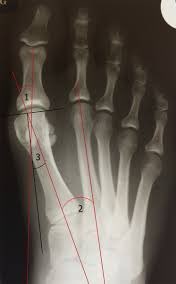

الأشعة:

-سيطلب منك جراح العظام إجراء سلسلة من الأشعة للقدم، ويجب أن تؤخذ والمريض واقف ثلاثة صور أمامية وجانبية ومائلة.

-يمكن طلب صورة للعظمتين السمسميتين حول إبهام القدم كذلك.

-سيقوم جراح العظام بحساب بعض الزوايا المهمة؛ لتحديد نوع العلاج اللازم.